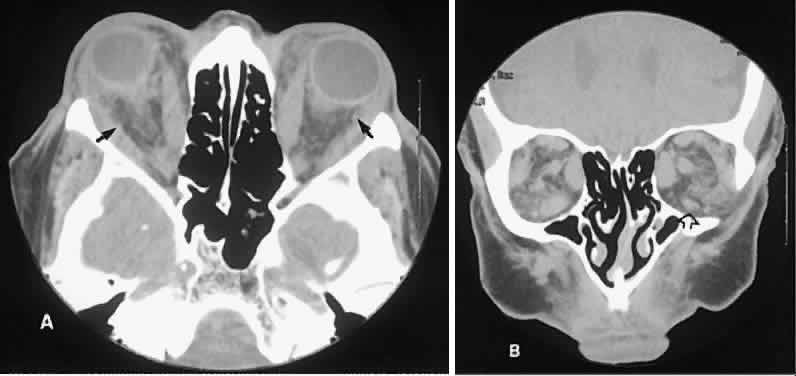

The muscle belly has a smooth contour with no edema of the adjacent orbital fat. We recently evaluated a patient with a referral diagnosis of Graves' orbitopathy. The patient was euthyroid but had severe orbital congestion typical of advanced Graves' orbitopathy. Imaging showed “dirty” orbital fat and lateral rectus muscle morphology that seemed atypical (Fig. 8). Biopsy specimen results showed a low-grade lymphoma. Hypertrophy of the medial rectus muscle can cause the medial wall to bow in toward the ethmoidal sinus from the chronic effects of pressure on the bone. The hypertrophied muscles also can give rise to a compressive optic neuropathy in the orbital apex as the enlarged muscles take their origin from the anulus of Zinn. Axial views of the apex show an apparent mass if the inferior rectus muscle is enlarged. It is imperative that additional views, sagittal or preferably coronal, be obtained to show the true nature of this apparent mass. Intracranial fat prolapse, seen by CT, may be another sign of optic neuropathy.44 An optic neuropathy also can be seen with relatively normal-sized EOM. An expanded fat compartment with optic nerve stretch has been associated with an optic neuropathy.45,46

Fig. 8. Low-grade lymphoma confined to orbit mistaken for Graves' ophthalmopathy in a 65-year-old man. A. On the axial view, orbital fat appears “dirty” with marked increase in soft tissue stranding. Muscles do not have a smooth appearance, lateral rectus muscles have lumpy appearance (arrow), and both lateral rectus muscles are disproportionately large for what typically is seen in Graves' orbitopathy. B. Coronal view also shows dirty orbital fat. Note left inferior rectus, which is small (arrowhead), and also is atypical in Graves' orbitopathy when there is enlargement of the other extraocular muscles.